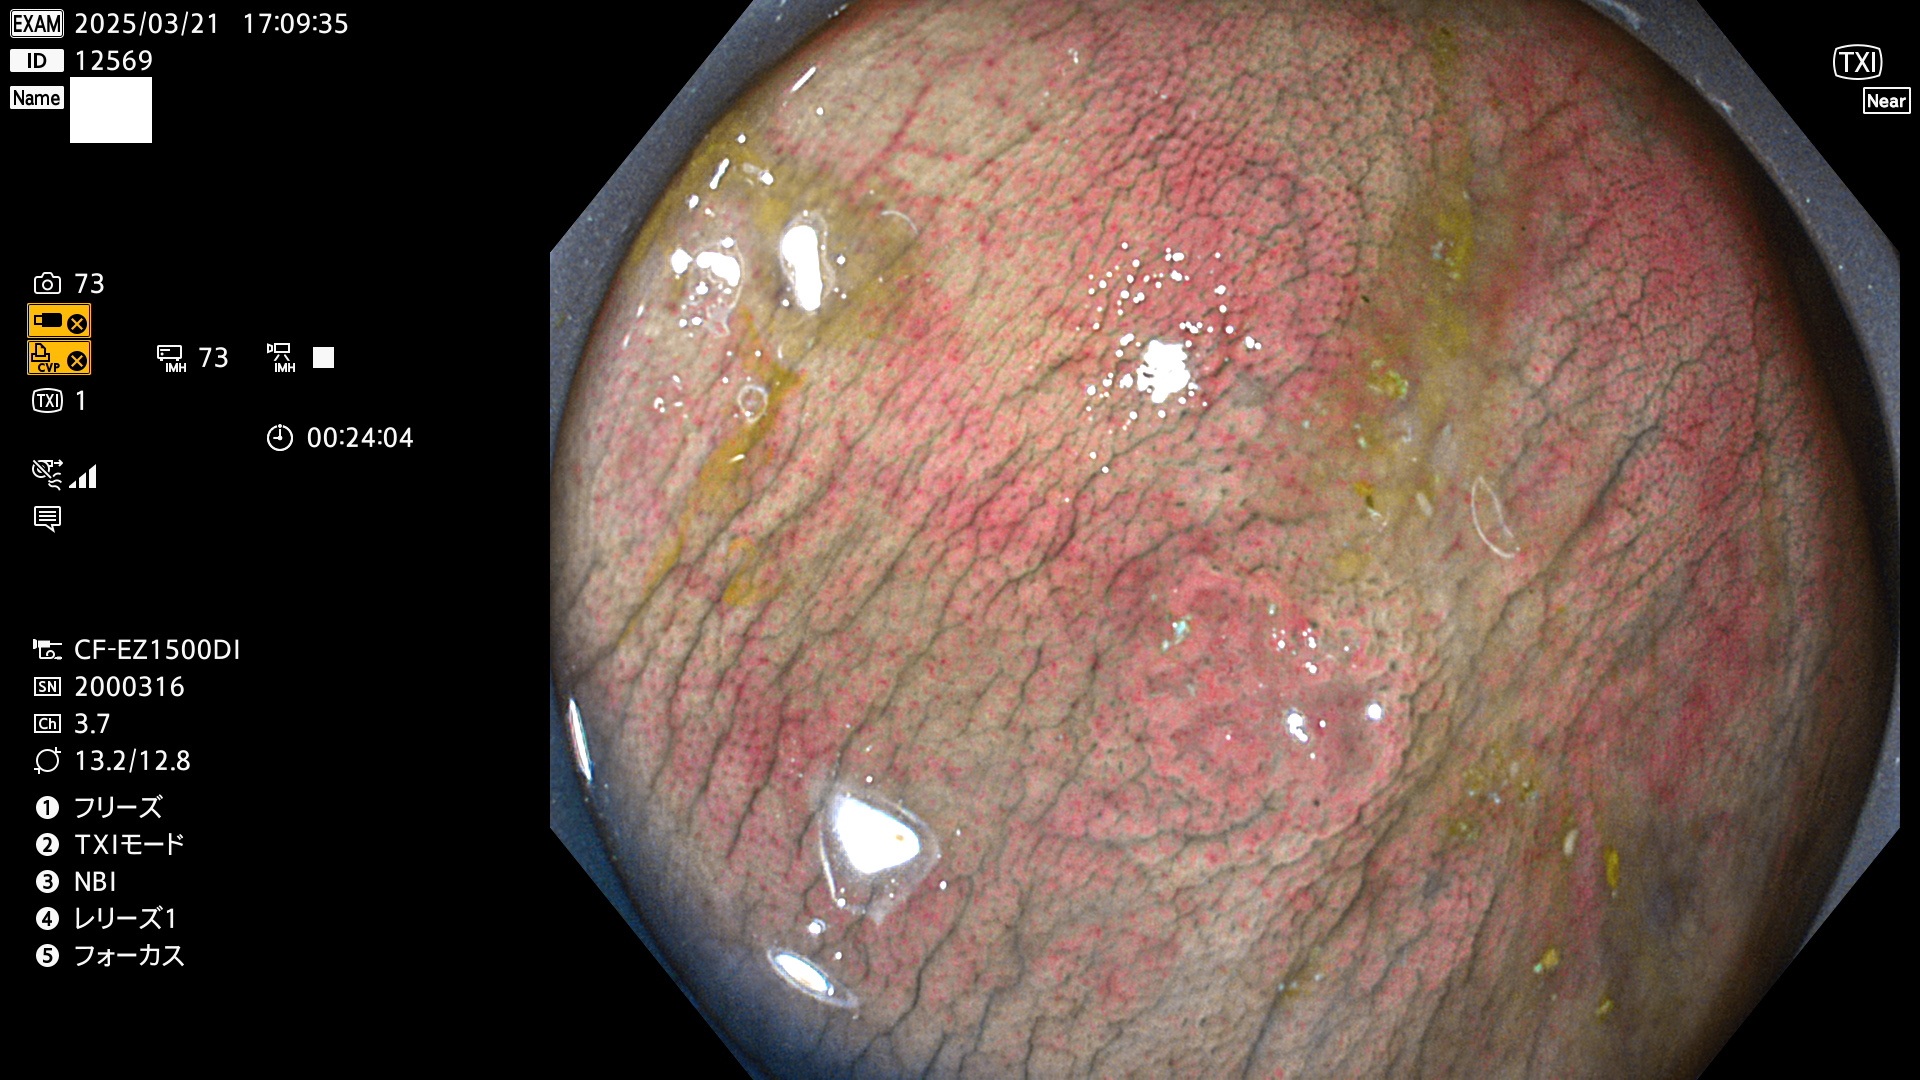

今週のUb、Uc型腺腫

完全に平坦な物をUb、陥凹している物をUcと呼びます。Ubは認識が困難で、Ucはびらん(炎症)と紛らわしいために見落とされやすく、「内視鏡後・大腸癌」の原因になります。

毎週の検査(木・金・土・日)に発見されたUb、Uc型・腺腫を、その週の日曜の夜にUPし1週間、提示します。

抽出の対象期間 2025年3月20日〜3月23日の4日間(48件の検査)10個 (10/48=21%)